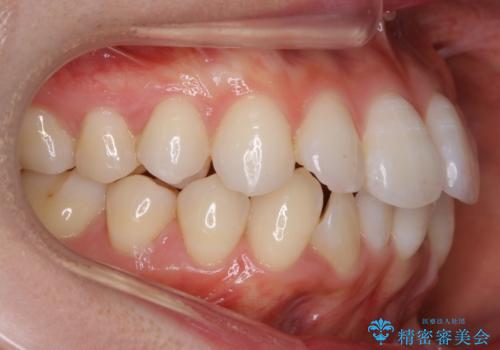

- 治療計画

ハーフリンガルとは上顎を裏側、下顎を表側のワイヤー装置で治療する場合をいいます。